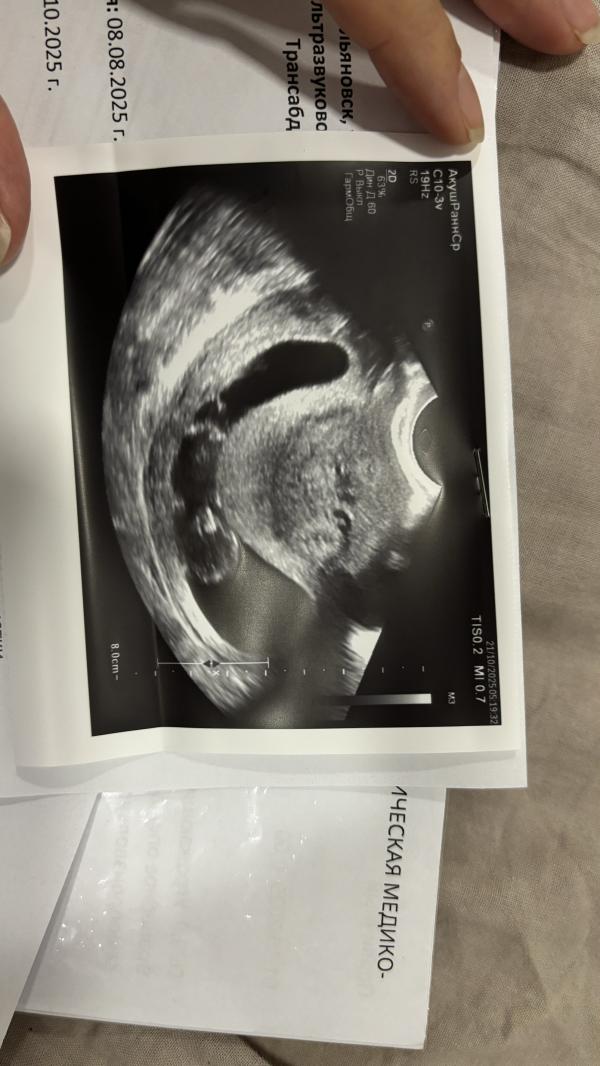

На узи гипертонус. Малыш развивается по сроку,шевелится,но матка так сжалась,что ему шевелиться негде. Сразу там же поставила магнезию. Повторили узи,стало чуть лучше,яйцо чуть округлилось.